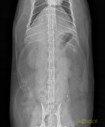

Quel est votre diagnostic ?

RadioQuiz 31 – Chien qui boite

RadioQuiz 30 – C’est parce qu’il fait frette que mon pitou tousse docteur ?

RadioQuiz 29 – Boiterie chronique